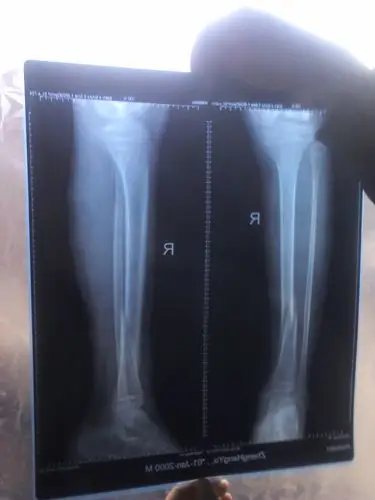

小腿左胫腓骨中下段粉碎骨折,保守治疗.

的dr正侧位x线照片:可以看出患者小腿胫腓骨双折,胫骨断段粉碎性骨折

术前x光片,胫腓骨双骨折,成角移位